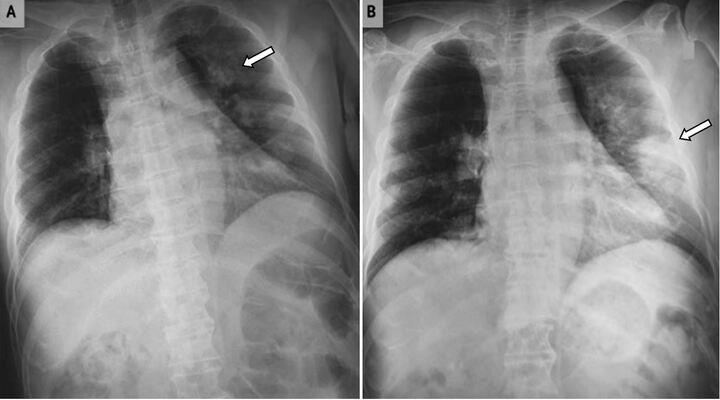

Nói đến bệnh xơ phổi, nhiều người thậm chí chưa từng nghe tên, nhưng tỉ lệ tử vong của căn bệnh này không hề thấp hơn ung thư phổi.

Tạp chí “American journal of case reports” (Mỹ) vừa công bố trường hợp đầu tiên trên thế giới ghép tế bào gốc chữa xơ phổi thành công được thực hiện tại Hệ thống y tế Vinmec, Hà Nội, Việt Nam; thành tựu đột phá của Vinmec đã tạo bước ngoặt lớn trong lĩnh vực nuôi dưỡng và chăm sóc trẻ sinh non yếu vốn thường xuyên phải đối mặt với nguy cơ tử vong do biến chứng của xơ phổi trên thế giới.